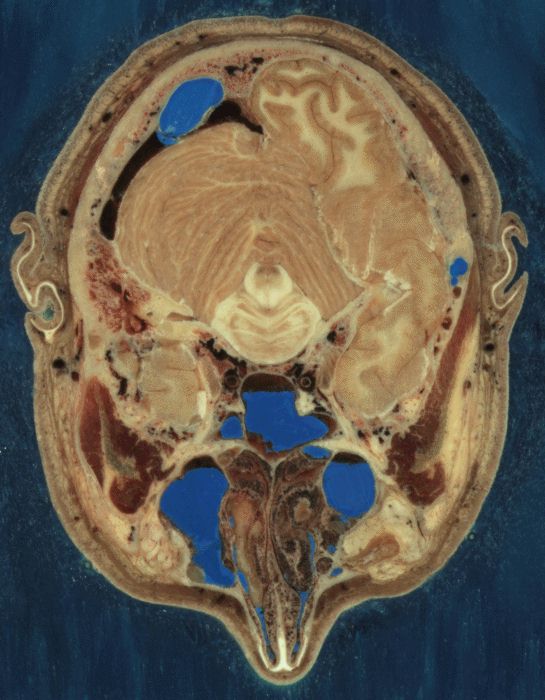

Corte transversal a través de la cabeza, incluye el cerebelo, corteza cerebral, tallo encefálico, fosas nasales.